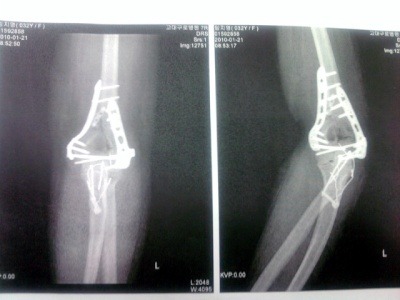

1/1일 넘어지면서 팔꿈치 8~10조각나서 분쇄 골절로 수술을 하였습니다.

대학병원에 재 입원 후 1/6일날 7시간의 대 수술을 하였습니다.

엑스레이나... CT상으로는 구부려 지지 않는 어떤 이유(?)가 발견되지 않는다고 하시면서 내복약 종류를 바꾸고 물리치료 꾸준히 받고.. 다시 2주 후에 뵙자고 하시네요..